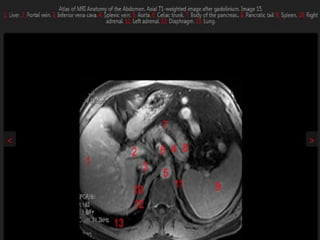

MRI anatomy images of the abdomen.

MRI anatomy imagesof the abdomen.